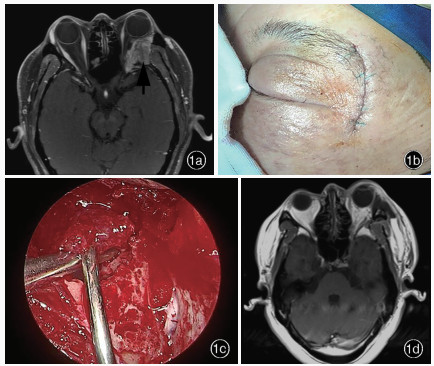

Han X , Yang H , Wang Z , Li L , Li C , Han S , Wu A . Endoscopic transorbital approach for skull base lesions: a report of 16 clinical cases. Neurosurg Rev, 2023, 46: 74.

doi: 10.1007/s10143-023-01980-y